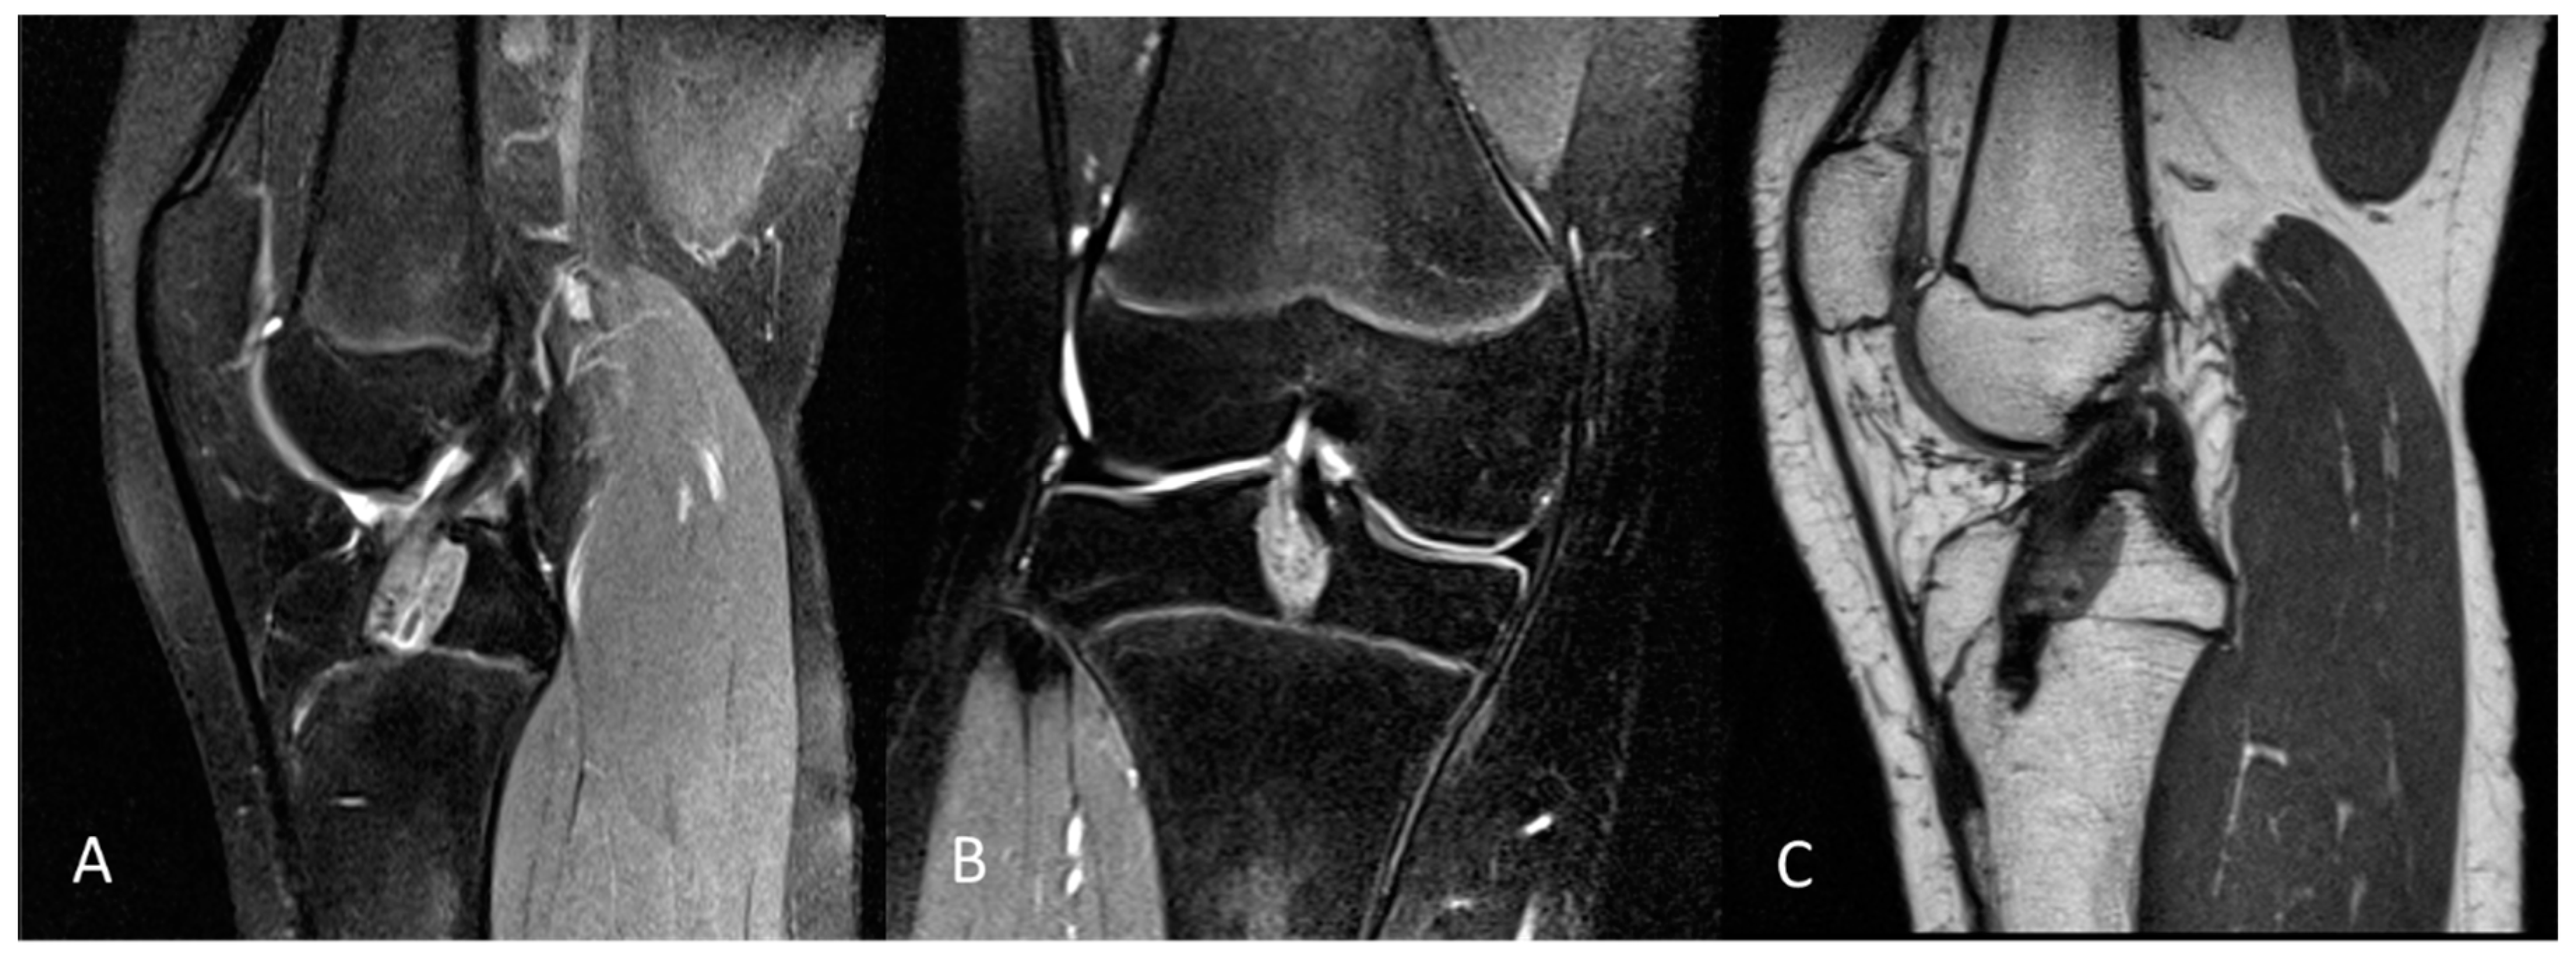

Tibial tunnel placement was perpendicular to the tibial physis to minimize physeal disruption. The femoral tunnel was drilled through an anteromedial portal with careful attention to avoid oblique positioning. The femoral socket was placed on the anatomical ACL footprint and drilled vertically to limit any damage to the growth plate. No osseous notchplasty was performed in each case. Graft fixation was achieved using an extracortical flip button for the femoral side, and tibial fixation was performed using a hybrid technique involving biodegradable interference screws and sutures over a bony bridge. An example of a postoperative MRI is shown in Figure 2.

Figure 2.

Example of a postoperative 3.0 Tesla knee MRI: (A) sagittal and (B) coronal PD tse fs, and (C) sagittal PD tse of a 14-year-old female patient with open physis and postoperative MRI after ACL reconstruction. PD tse fs (proton density-weighted turbo spin echo sequence with fat saturation), PD tse (proton density-weighted turbo spin echo sequence).